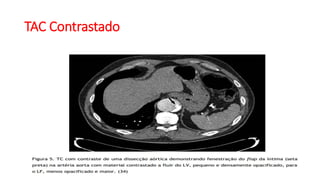

TAC Contrastado

TAC Contrastado(Cont.)